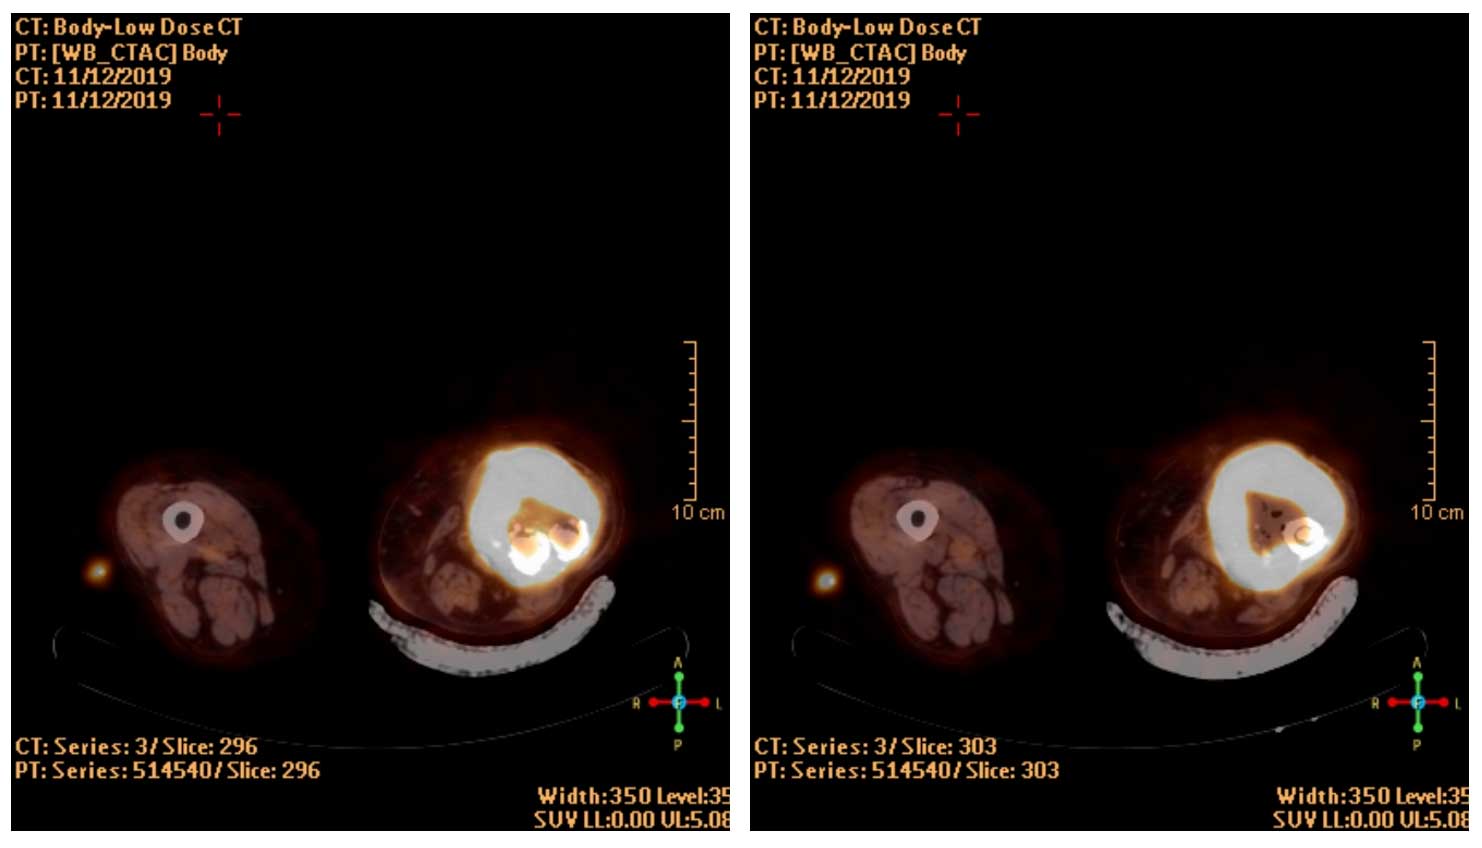

Ameliyat Öncesi: PET-CT’de yoğun artmış aktivite görülmekte.